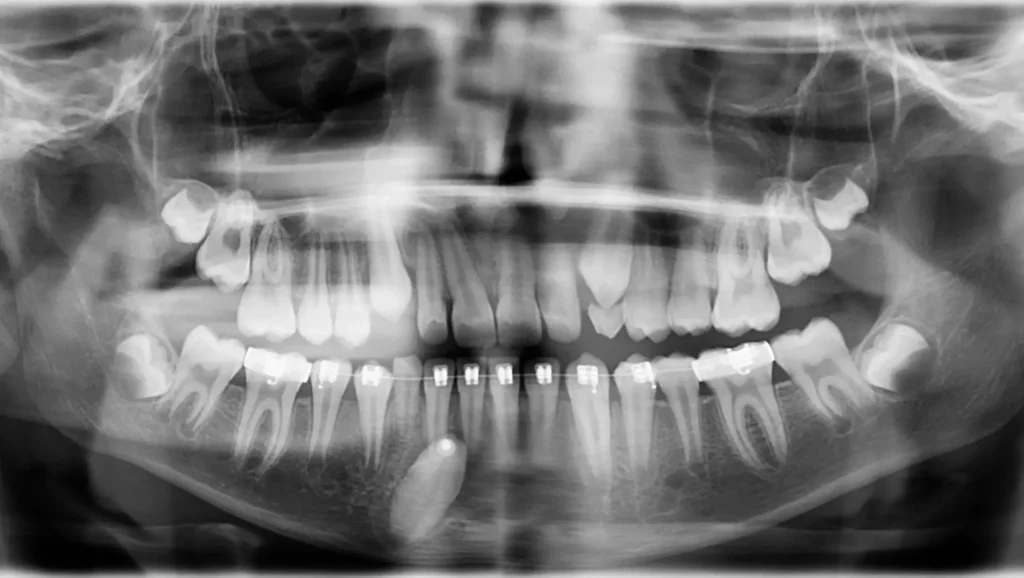

El tratamiento de ortodoncia se dividió en tres fases:

1- Fase inicial: creación de espacio

2- Fase de tracción del canino impactado:

3- Fase de finalización y detallado: